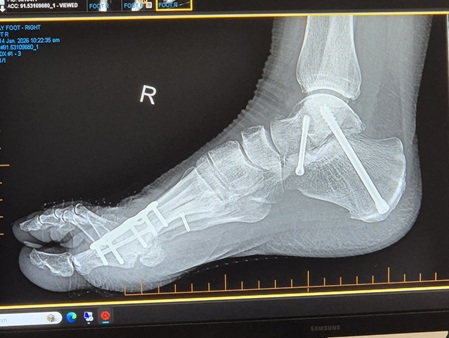

I returned from Aotearoa New Zealand in November and starting physically preparing for the scheduled second ankle fusion (that took place December 2). Readers who have had an ankle fusion or read about my first ankle fusion will know that while the final outcome is fantastic, the post-op period is a nightmare!

- 2 weeks in a plaster cast, operated foot elevated 23 hours of every day (in a rehab hospital)

- 4 weeks in a fibreglass cast, non-weight bearing so on a knee scooter

- At the 6 week mark, x-ray, review by surgeon, if all good promotion to a moonboot

- 4 weeks in a moonboot, with crutches for the first 3 weeks as the weight bearing is increased slightly each week

- At the start of week 11 you can actually migrate to runners! Yay!

- At the end of week 12 another review by the surgeon and hopefully you are set free: with some restrictions.